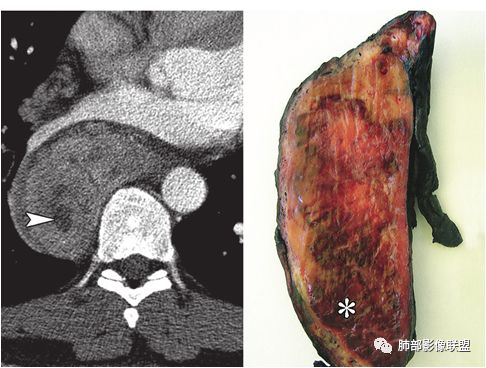

结果:巨大淋巴结增生病(Castleman,s, disease,CD)

(2)根据组织学特点分为透明血管型和浆细胞型两个基本类型,组织学共同点为具有完整的淋巴结结构、淋巴滤泡增生及血管增生

(3)影像表现上,多发单发的圆形或类圆形软组织密度影;透明血管型在CT增强扫描时早期可显著均匀强化,与大血管强化程度相似,原因在于有较多的供养血管,及病灶的毛细血管异常增生和扩展所致;而浆细胞型强化没有前者明显

(4)文献图片(A:透明血管型)